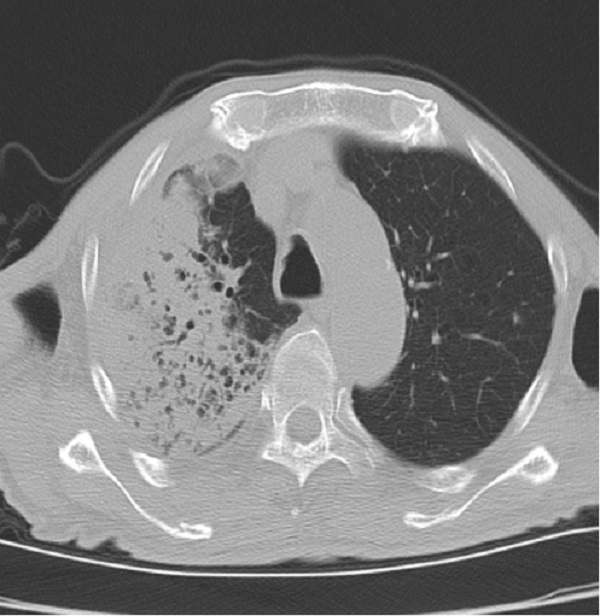

许爷爷今年83岁,不慎摔伤致左髋部疼痛入住二一五医院骨五科,完善检查发现许爷爷新冠病毒检测为阳性,肺部已有感染。由于年事已高,有基础病且合并新冠病毒感染,病情复杂危重,情况非常棘手。骨五科潘建宏主任团队为许爷爷进行了全面细致的病情评估,并请院内相关专家组会诊,制定了有针对性的治疗方案。